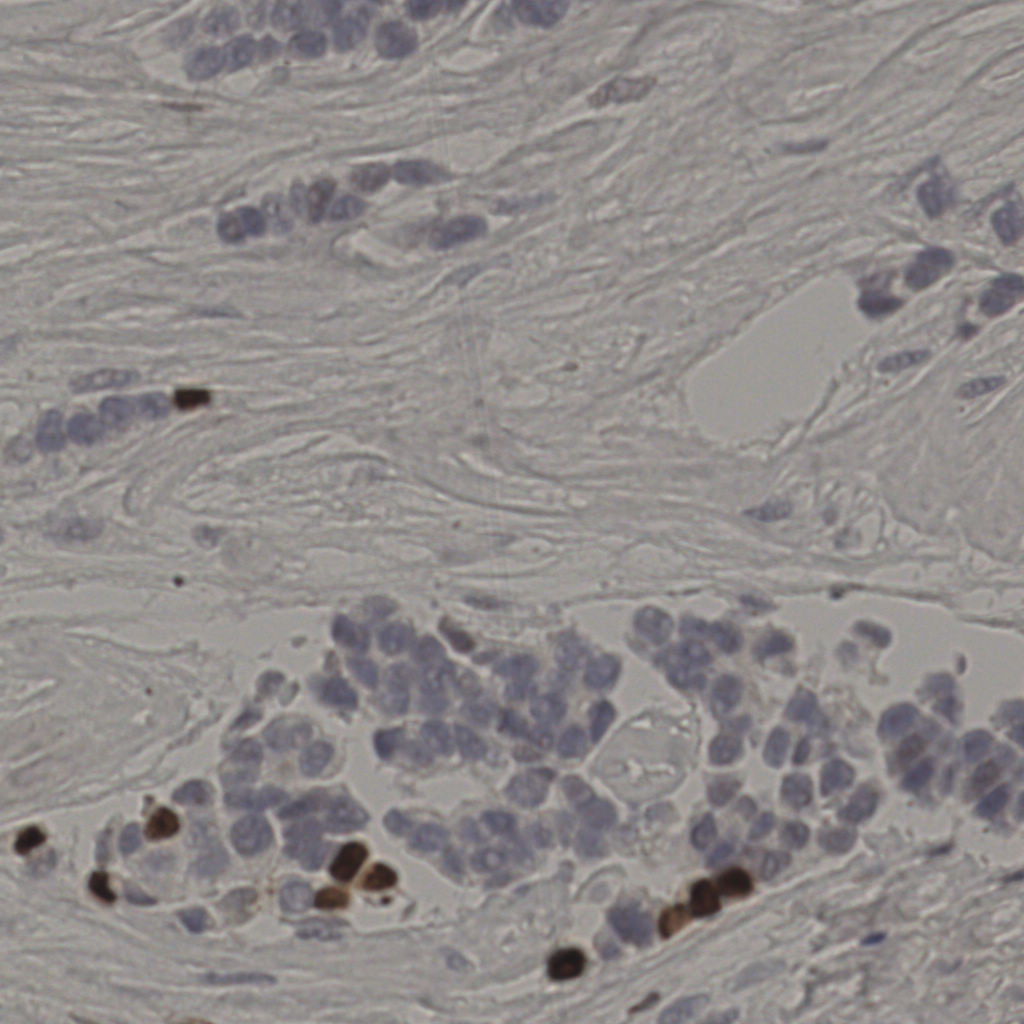

17.75%

Ki67 指数

阴 7986 阳 1723

切片统计

总切片 2640

有效 412

已标记 412

有效率 16%

20240285Ki-67.ndpi